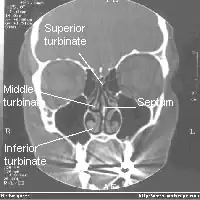

Sur les côtés latéraux on a trois cornets qui offrent une résistance à l'écoulement de l'air et le dirigent vers l'épithélium olfactif en haut.

Il y a trois cornets dans chaque cavité nasale :

- le cornet inférieur : le plus grand, aussi long que l'index;

- le cornet moyen : aussi long qu'un auriculaire ;

- le cornet supérieur : très petit.

Les deux cavités nasales sont séparées par la cloison nasale appelée septum.

Les cornets divisent les voies respiratoires nasales en 3 passages aériens semblables à des sillons, les méats inférieur, moyen et supérieur, forçant ainsi l'air turbulent à s'écouler selon un flux laminaire autour de la plus grande surface possible de cils et de tissu. Les cornets sont essentiellement le radiateur et le moteur du nez.

Les cornets inférieurs, les plus grands, sont les principaux tissus humidifiants, réchauffants, filtrants et orienteurs du flux aérien.

La majeure partie du flux d'air inhalé voyage dans le méat moyen, entre les cornets inférieurs et les cornets moyens.

Les cornets moyens sont plus petits et se projettent vers le bas à partir des sinus ethmoïdes. Ils abritent les ouvertures jusqu'aux maxillaires et aux sinus ethmoïdes et agissent comme des tampons d'air pour que les sinus ne soient pas en contact direct avec le flux d'air pressurisé nasal.

Les cornets supérieurs protègent le bulbe olfactif et sont également innervés avec une multitude de terminaisons nerveuses olfactives qui se prolongent quelque part dans les cornets moyens.